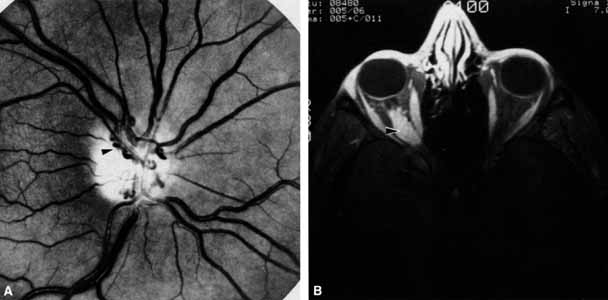

Anosmia caused by damage of cranial nerve I may be a helpful symptom of ethmoid or sphenoid sinus tumors invading the orbit (Fig. 20).44 Olfactory groove meningiomas and esthesioneuroblastomas may also present with anosmia prior to developing vision loss.45 Trauma that involves the orbit and is associated with anosmia should be considered a basilar skull fracture with potential for cerebrospinal fluid leak until proven otherwise (Fig. 21).

Fig. 20 A 13-year-old child presented with a 2-week history of sinusitis and anosmia. Her visual acuity decreased to to 20/400 1 day prior to admission. Computed tomography shows a large ethmoid tumor extending through the cribriform plate and optic canal. A rhabdomyosarcoma was diagnosed by biopsy.

Fig. 21 A 21-year-old man sustained a skull fracture from a motor vehicle accident 2 months prior to this examination. The patient describes anosmia since the accident. Computed tomography discloses a large medial wall orbital fracture extending through the cribriform plate (arrow). Orbital reconstruction was performed through a frontal craniotomy where dura was found incarcerated within the fracture. The orbital fracture was repaired by cranial bone grafting.